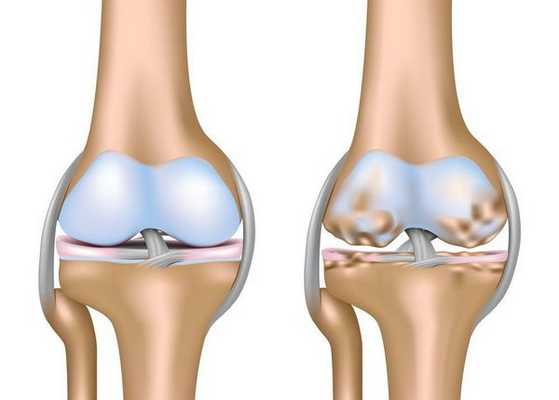

Артроз коленного сустава (гонартроз) — это прогрессирующее хроническое заболевание коленных суставов с повреждением, истончением и разрушением его хрящевой части (суставные поверхности бедренной и большеберцовой костей), а также поражением субхондральной кости. [2] [5] [16] Доказано исследованиями (артроскопия и МРТ), что помимо поражения суставного хряща в процесс вовлекаются мениски и синовиальная оболочка. Гонартроз — одна из самых распространенных ортопедических патологий. [4] [6] [9] [22] Существуют его синонимы — остеоартроз (ОА), деформирующий артроз. Заболевание является важной социально-экономической проблемой, так как широко распространено и значительно ухудшает качество жизни больных из-за постоянного болевого синдрома и, кроме того, становится причиной высокой инвалидизации. [15] [27]

До середины восьмидесятых годов прошлого века не было унифицированного определения заболевания. Только к 1995 году комитетом по остеоартрозу Американского колледжа ревматологии заболевание было охарактеризовано как результат действия механического и биологического факторов, приводящих к дисбалансу между процессами деградации и синтеза внеклеточного матрикса суставного хряща. [11] [19] В итоге происходит его разволокнение и дегенерация, образуются трещины, остеосклероз и уплотнение кортикального слоя субхондральной кости, растут остеофиты и формируются субхондральные кисты. [12] [29]

Гонартроз, I стадия

Первая стадия заболевания характеризуется первичными изменениями в гиалиновом хряще. [12] [18] Костные структуры не затрагиваются. Во внутрикостных сосудах и капиллярах нарушается кровоснабжение. Становится сухой поверхность хряща, и он утрачивает свою гладкость. Если заболевание сопровождается постоянным напряженным синовитом, то развивается киста Бейкера (грыжевое выпячивание капсулы сустава подколенной области). [15] После значительной нагрузки на сустав возникают тупые боли. Возможна небольшая отечность, которая проходит после отдыха. Деформации нет.

Гонартроз, II стадия

На второй стадии хрящевая прослойка резко истончается, а местами и вовсе отсутствует. [22] Появляются остеофиты по краям суставных поверхностей. Изменяются качественные и количественные характеристики синовиальной жидкости сустава — она становится гуще, более вязкой, что приводит к ухудшению питающих и смазывающих свойств. [14] [16] Боли более продолжительные и интенсивные, часто при движении появляется хруст. Отмечается незначительное или умеренное ограничение движений и небольшая деформация сустава. Прием анальгетиков помогает снять болевой синдром.

Гонартроз, III стадия

Отсутствие хряща на большинстве поражённых участков, выраженный склероз (уплотнение) кости, множество остеофитов и резкое сужение или отсутствие суставной щели. [8] [15] Боли практически постоянные, походка нарушена. Подвижность резко ограничена, заметна деформация сустава. Препараты НПВС, физиопроцедуры и другие стандартные методы лечения артроза коленного сустава неэффективны. [11]